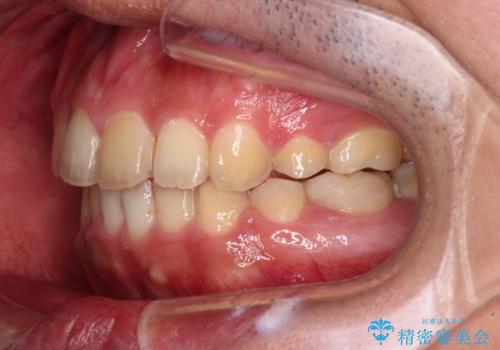

後戻りでデコボコの前歯 インビザライン矯正治療

- 高校時代に行った抜歯矯正が後戻りをしたとのことで来院された患者様です。

再矯正であることから、目立ちにくい装置を希望されたため、インビザラインにて矯正治療を行うこととしました。

下顎骨が左側に変位しているため、正中が合わないことは予想できましたが、歯列が整った後も咬み合わせが安定せず、咬み合わせを落ち着かせるために1年以上の期間を要しました。